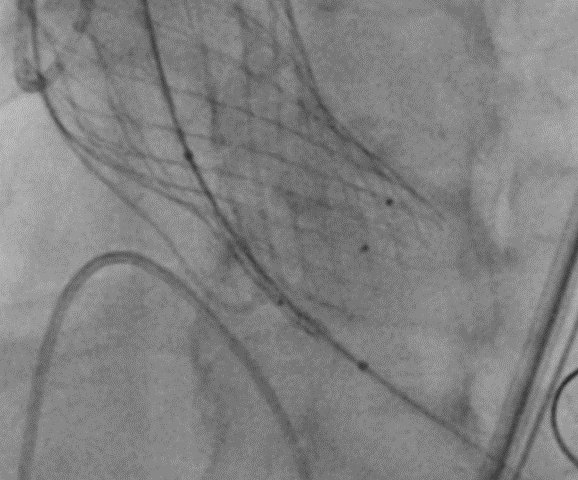

手术开始后,按照术前制定的方案,金泽宁教授团队经由患者左股动脉送入脑保护装置,使脑保护装置完全覆盖头臂动脉、左颈总动脉、左锁骨下动脉开口。然后经由右股送入23球囊,预扩之后,植入L26型号的人工主动脉瓣瓣膜,置入瓣膜之后压差和流速均下降,患者血流动力学效果良好。随后撤出脑保护装置,术中未出现并发症。